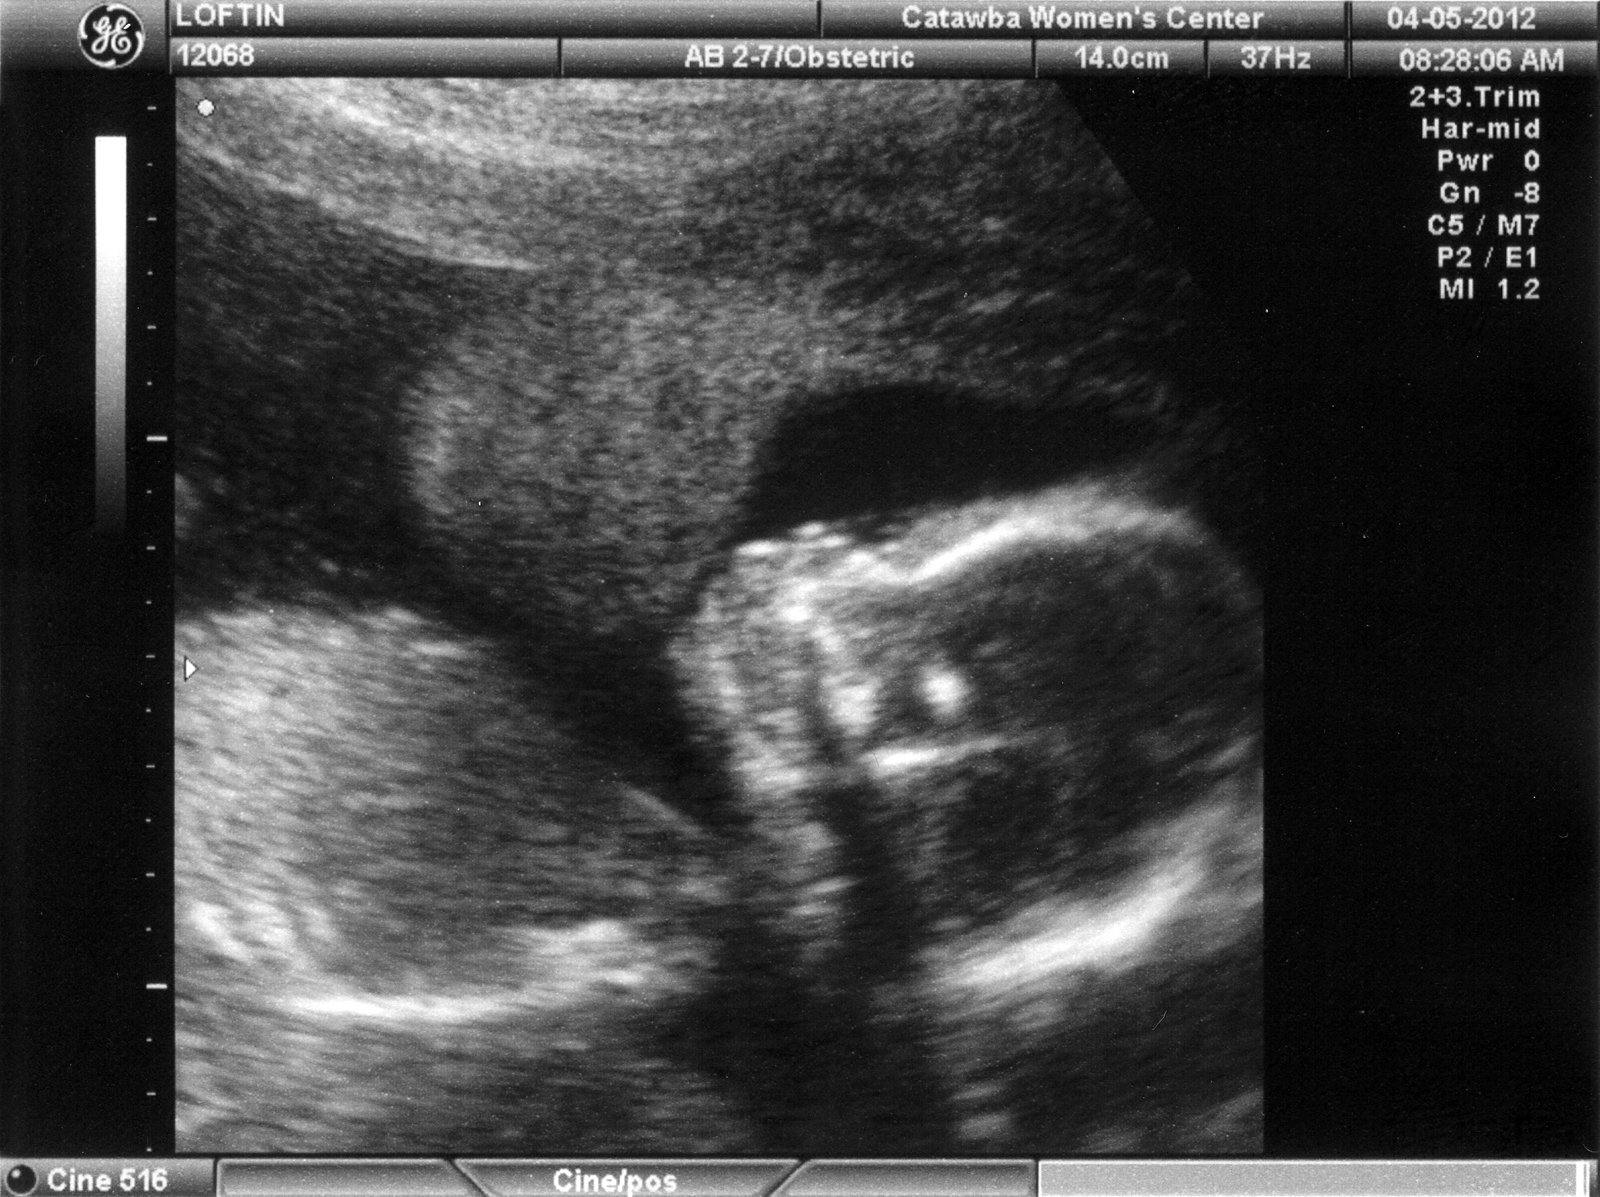

Taken at 18 weeks

These pictures are from Apr 5, 2012.